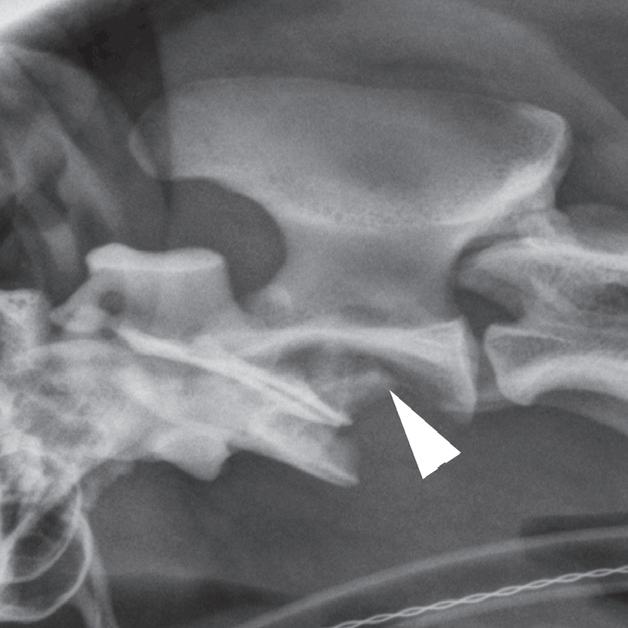

Badanie wykonano u 2-letniej samicy owczarka australijskiego z bólem odcinka szyjnego kręgosłupa, ale bez deficytów neurologicznych, która 9 dni przed badaniem wpadła na ogrodzenie. Obrazy przedstawione na ryc. a–c ułożono od strony czaszkowej do ogonowej na poziomie zęba obrotnika (a – grot strzałki), doczaszkowej części C2 oraz środkowej części trzonu C2. Obraz na ryc. d to rekonstrukcja w płaszczyźnie strzałkowej przez linię pośrodkową, a na ryc. e zamieszczono obraz wykonany w pobliżu płaszczyzny strzałkowej obejmujący ząb obrotnika (e – grot strzałki). Widać przemieszczenie skośnego złamania trzonu kręgu obrotowego (axis) (b–f – strzałka). Przemieszczenie fragmentu złamania względem atlasu powoduje znaczne zmniejszenie średnicy kanału kręgowego (b – gwiazdka). Złamanie jest widoczne na radiogramie (g – grot strzałki), jednak poziomu zwężenia kanału kręgowego nie da się ocenić równie dokładnie jak na obrazach TK. Ze względu na upływ czasu od urazu i brak objawów neurologicznych pacjentkę leczono zachowawczo, jednak właściciel zwierzęcia nie zgłosił się na dalsze wizyty kontrolne